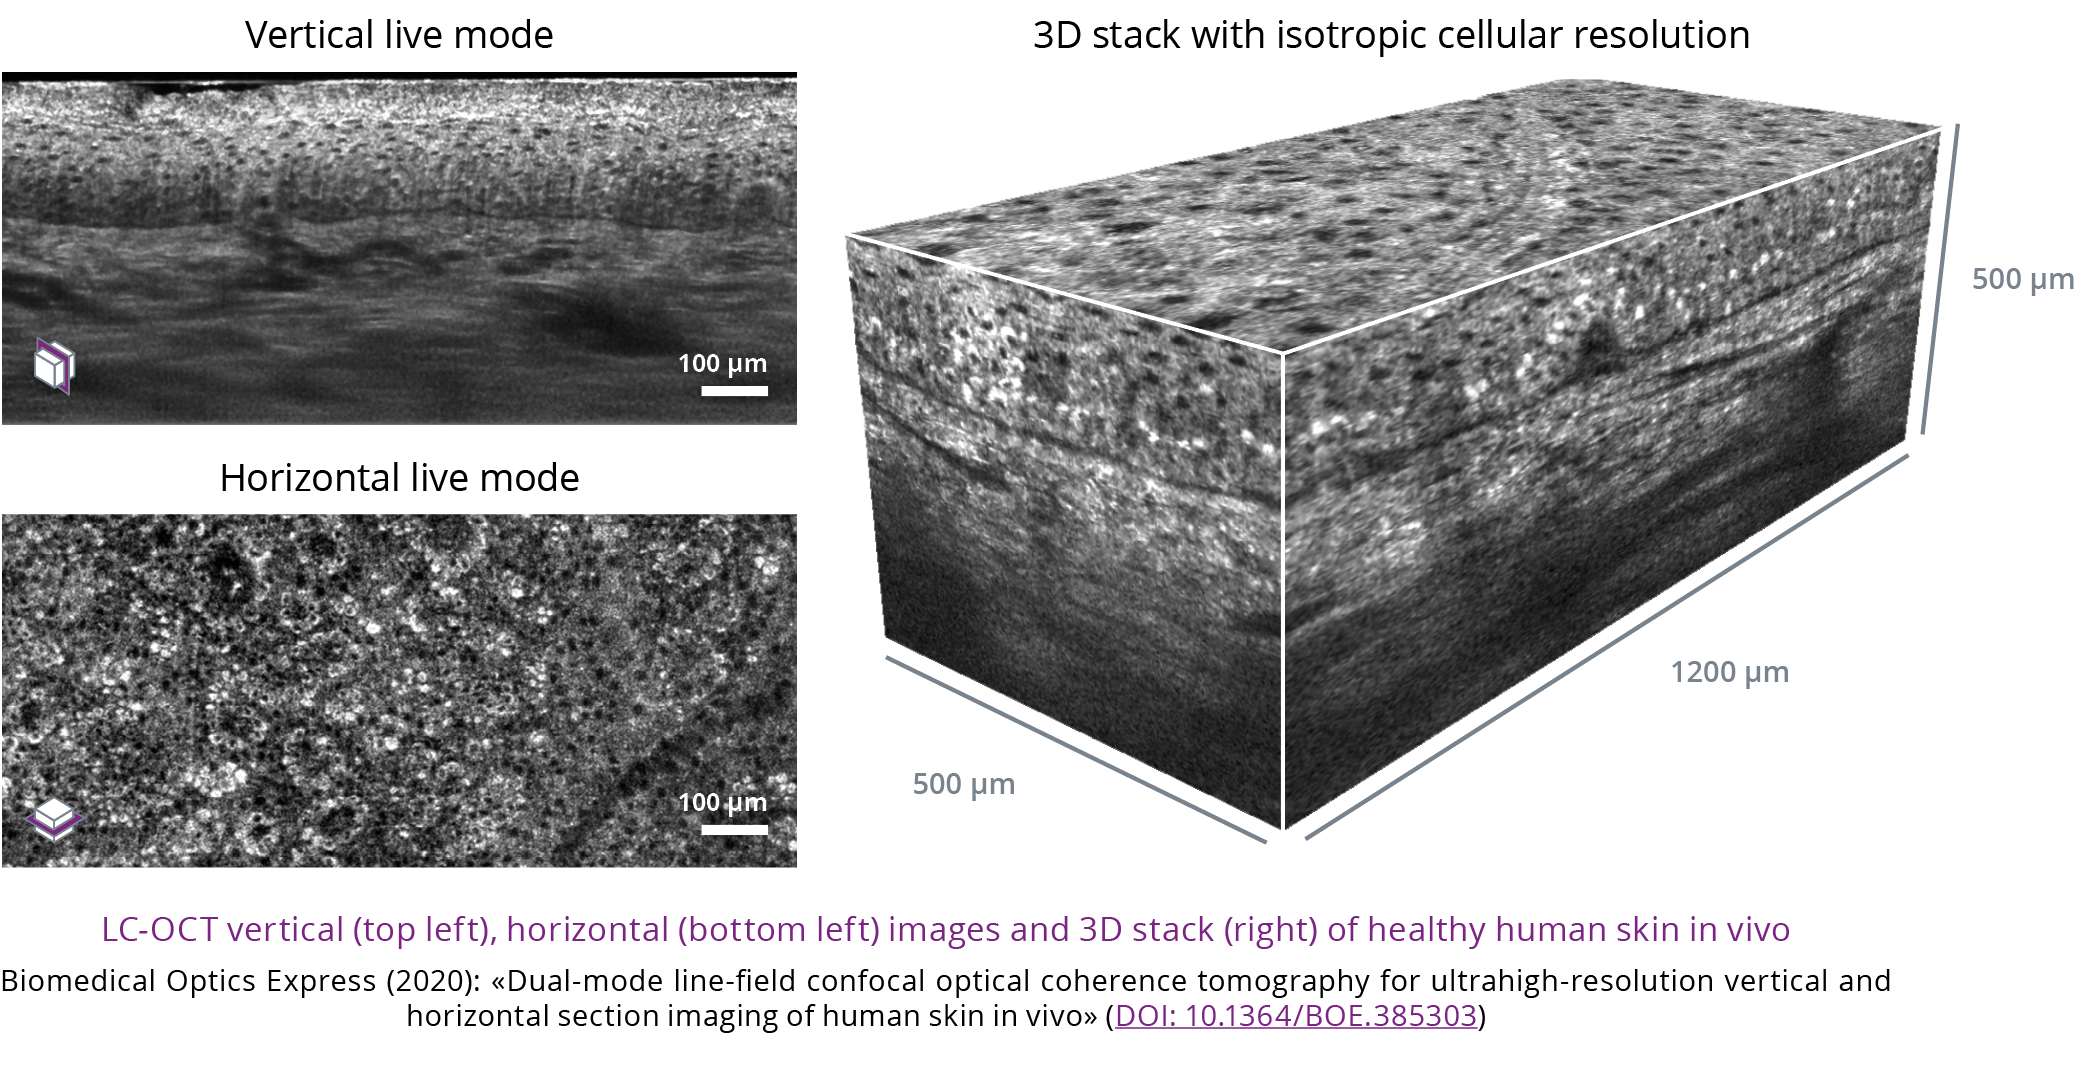

deepLive™ integrates LC-OCT (Line-field Confocal Optical Coherence Tomography) technology which provides a unique 3D imaging modality, allowing the user to switch from a histology-like vertical mode to a confocal-like horizontal mode,

and to record a 3D stack of tissue volumes in situ.